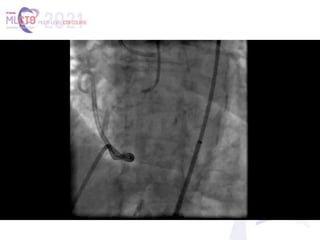

(A, B) The proximal right coronary artery (RCA) occlusion, visualized with separate antegrade and retrograde contrast

injections. Side branch–like, tortuous, continuous transseptal collaterals from the left anterior descending coronary

artery (LAD) supply the distal RCA (white arrow). Notice the mid-LAD severe focal stenosis (yellow arrow). (C) Lesion was

assumingly crossed by antegrade wire escalation, facilitated by proximal anchor technique. Notice the guidewire course

mimicking the imaginary contour of the native RCA artery. Crossing was not confirmed by contralateral injection, and 2

compliant balloons were inflated to dilate the lesion (white arrow). (D) Ellis type III coronary perforation into the

pericardial space (red arrow). (E) Delivery of the microcatheter to the distal cap (white arrow), following proximal

balloon inflation and placement of a pigtail pericardiocentesis catheter. Notice the ectopic guidewire into the

pericardium (red arrows). (F) Wire system externalization through the crossed lesion and the transiently deflated

proximal balloon (white arrow). (G, H) Final result. Sealing by deploying 2 drug-eluting stents, overlapping at the area of

the perforation. The mid-LAD lesion was treated with a drug-eluting stent with a similarly excellent result.